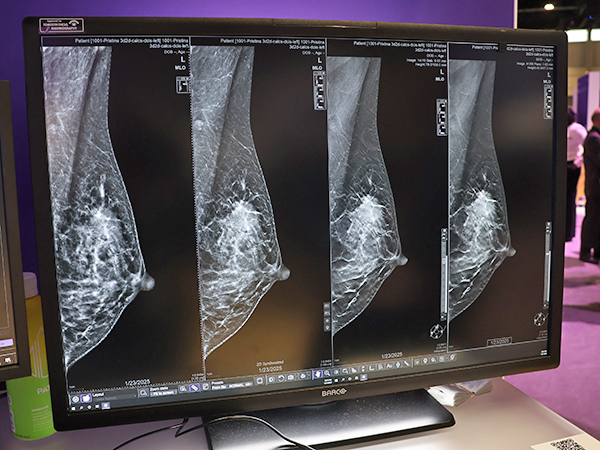

GE HealthCare(GEヘルスケア)のWomen’s Healthコーナーでは前回発表したデジタルマンモグラフィ「Pristina Via」の最新バージョン(薬機法未承認)のアンベールイベントを行い,新たに搭載されるディープラーニング技術を応用した3Dマンモグラフィ画像再構成技術「Pristina Recon DL」(薬機法未承認)をアピールした。RSNA 2025前に,米国食品医薬局(FDA)の承認を得たばかりの新技術で,乳房トモシンセシス(DBT)において,低線量での撮影でも高画質画像を得られる。ディープラーニング技術は高精度な3D画像再構成を行い,ノイズを抑えてアーチファクトを抑制する。Pristina Recon DLでは,合成2D画像とplaneとslabの3D画像の3種類の画像を出力する。従来,トモシンセシス画像の読影には時間を要していたが,Pristina Recon DLによって読影の負担軽減につながることが期待される。

「Pristina Recon DL」(薬機法未承認)により微細な石灰化や腫瘤の描出能が向上